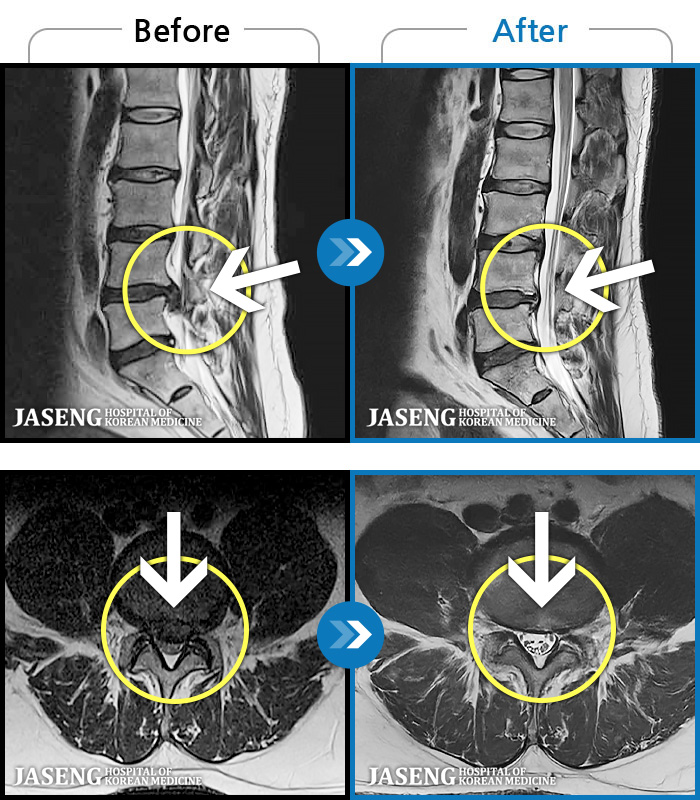

ó 㸮 , ٸ ϰ ־ Ȱ , ߰ ᵵ ڰ Ͽ Ȱ ¼̽ϴ. |